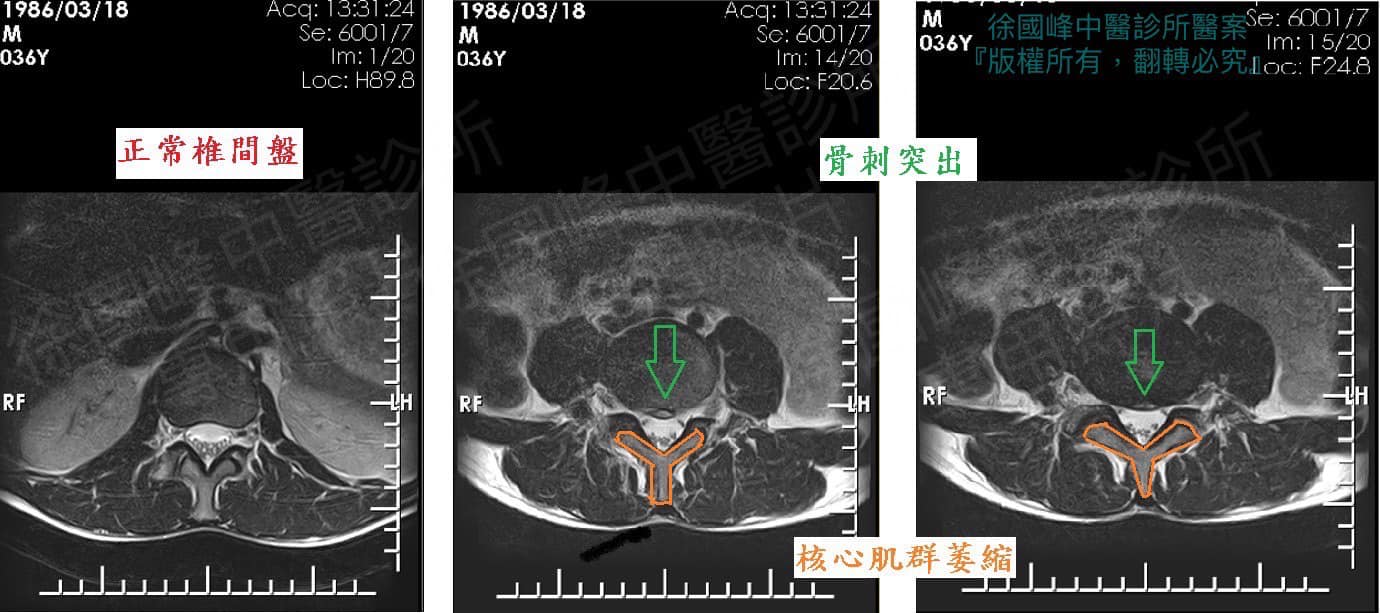

1.L3L4;L4L5;L5S1輕微HIVD

2.豎直肌慢性筋膜發炎疼痛

一般來說,單純的脊椎狹窄壓迫神經,是因為長期彎腰導致脊椎兩旁的黃韌帶(ligamentum flavum)肥厚增生進而壓迫到神經,只要未伴隨脊柱嚴重滑脫,通常只要將黃韌帶減壓,讓神經不再受到壓迫即可,之後訓練患者核心肌群,讓筋膜當作自己的最強骨架,原則上開刀是最後最後要選的路。